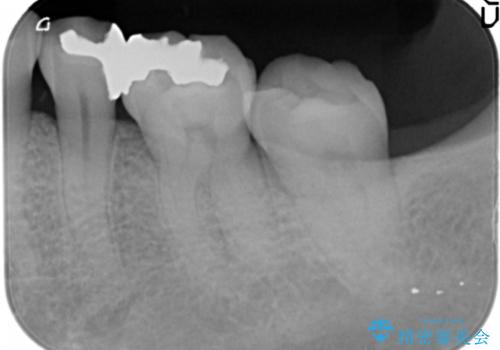

- 銀の詰め物が気になるとのことで来院。

2本隣り合っているつめものを、同時にやりかえをしました。

- 14万円(左下5・左下6 emaxプレスインレー 7万円 x 2)費用は治療当時の料金となります

向かい合う銀歯を同時にやり変えることで、コンタクト(歯と歯の間の形)を理想的に仕上げることができ、ものも挟まりにくいように仕上げることができます。